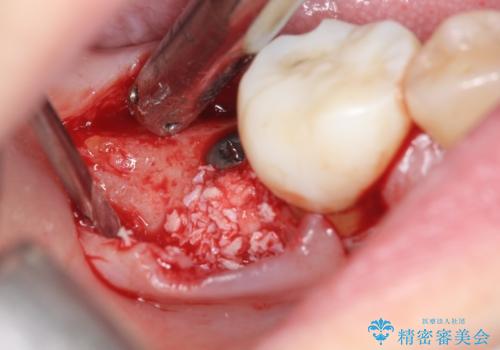

- 歯を欠損し、噛めないことの治療を希望され来院されました。

インプラントを用いて、しっかりとかめるような治療を計画します。

- 45万円(ストローマンインプラント・骨造成・チタンカスタムアバットメント・ジルコニアクラウン)費用は治療当時の料金となります

最後方臼歯はインプラントを用いることでしっかりと咬合機能を回復することができます。

- 外科手術のため、術後に痛みや腫れ、違和感を伴います